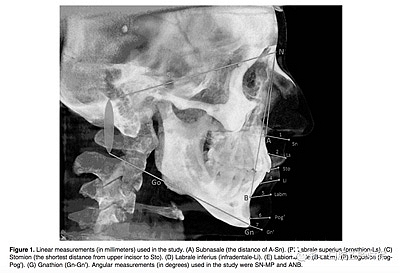

所有患者拍攝頭顱CBCT,要求以最大的牙尖交錯(cuò)位, 放松嘴唇位置, 不能移動(dòng)他們的頭部或舌頭。CBCT圖像被轉(zhuǎn)化為數(shù)字成像, 然后使用 Simplant Pro 軟件測(cè)量軟組織厚度 和角度的測(cè)量,測(cè)量指標(biāo)見Figure 1。所有厚度測(cè)量都是隨機(jī)盲法下由經(jīng)驗(yàn)豐富的不知道病人生長型的口腔放射科醫(yī)生測(cè)量。頭影測(cè)量是由牙醫(yī)測(cè)量。